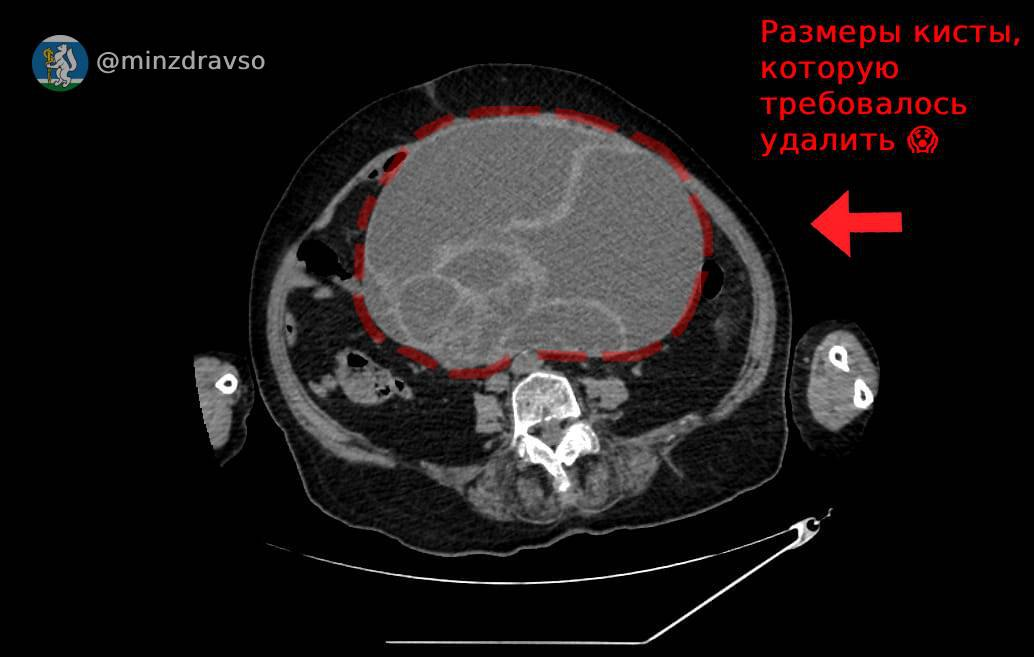

Специалисты Красноуфимской районной больницы Свердловской области провели сложную операцию по удалению огромной кисты у 86-летней пациентки. Образование размером 32х25х22 сантиметра и весом 4,5 килограмма сдавливало внутренние органы, угрожая жизни женщины.

По словам заведующего отделением акушерства и гинекологии Юрия Шахурина, такие крупные кисты встречаются крайне редко, и их наличие может вызвать серьезные осложнения. В случае пациентки киста перекрутилась, что привело к некрозу тканей и риску перитонита.